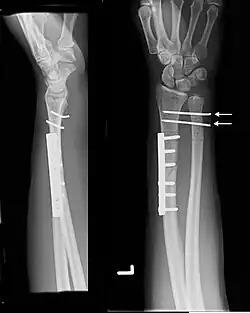

Galeazzi fracture. Arrow points at the dislocated ulnar head | |

The Galeazzi fracture is a fracture of the distal third of the radius with dislocation of the distal radioulnar joint. It classically involves an isolated fracture of the junction of the distal third and middle third of the radius with associated subluxation or dislocation of the distal radio-ulnar joint; the injury disrupts the forearm axis joint.[1]